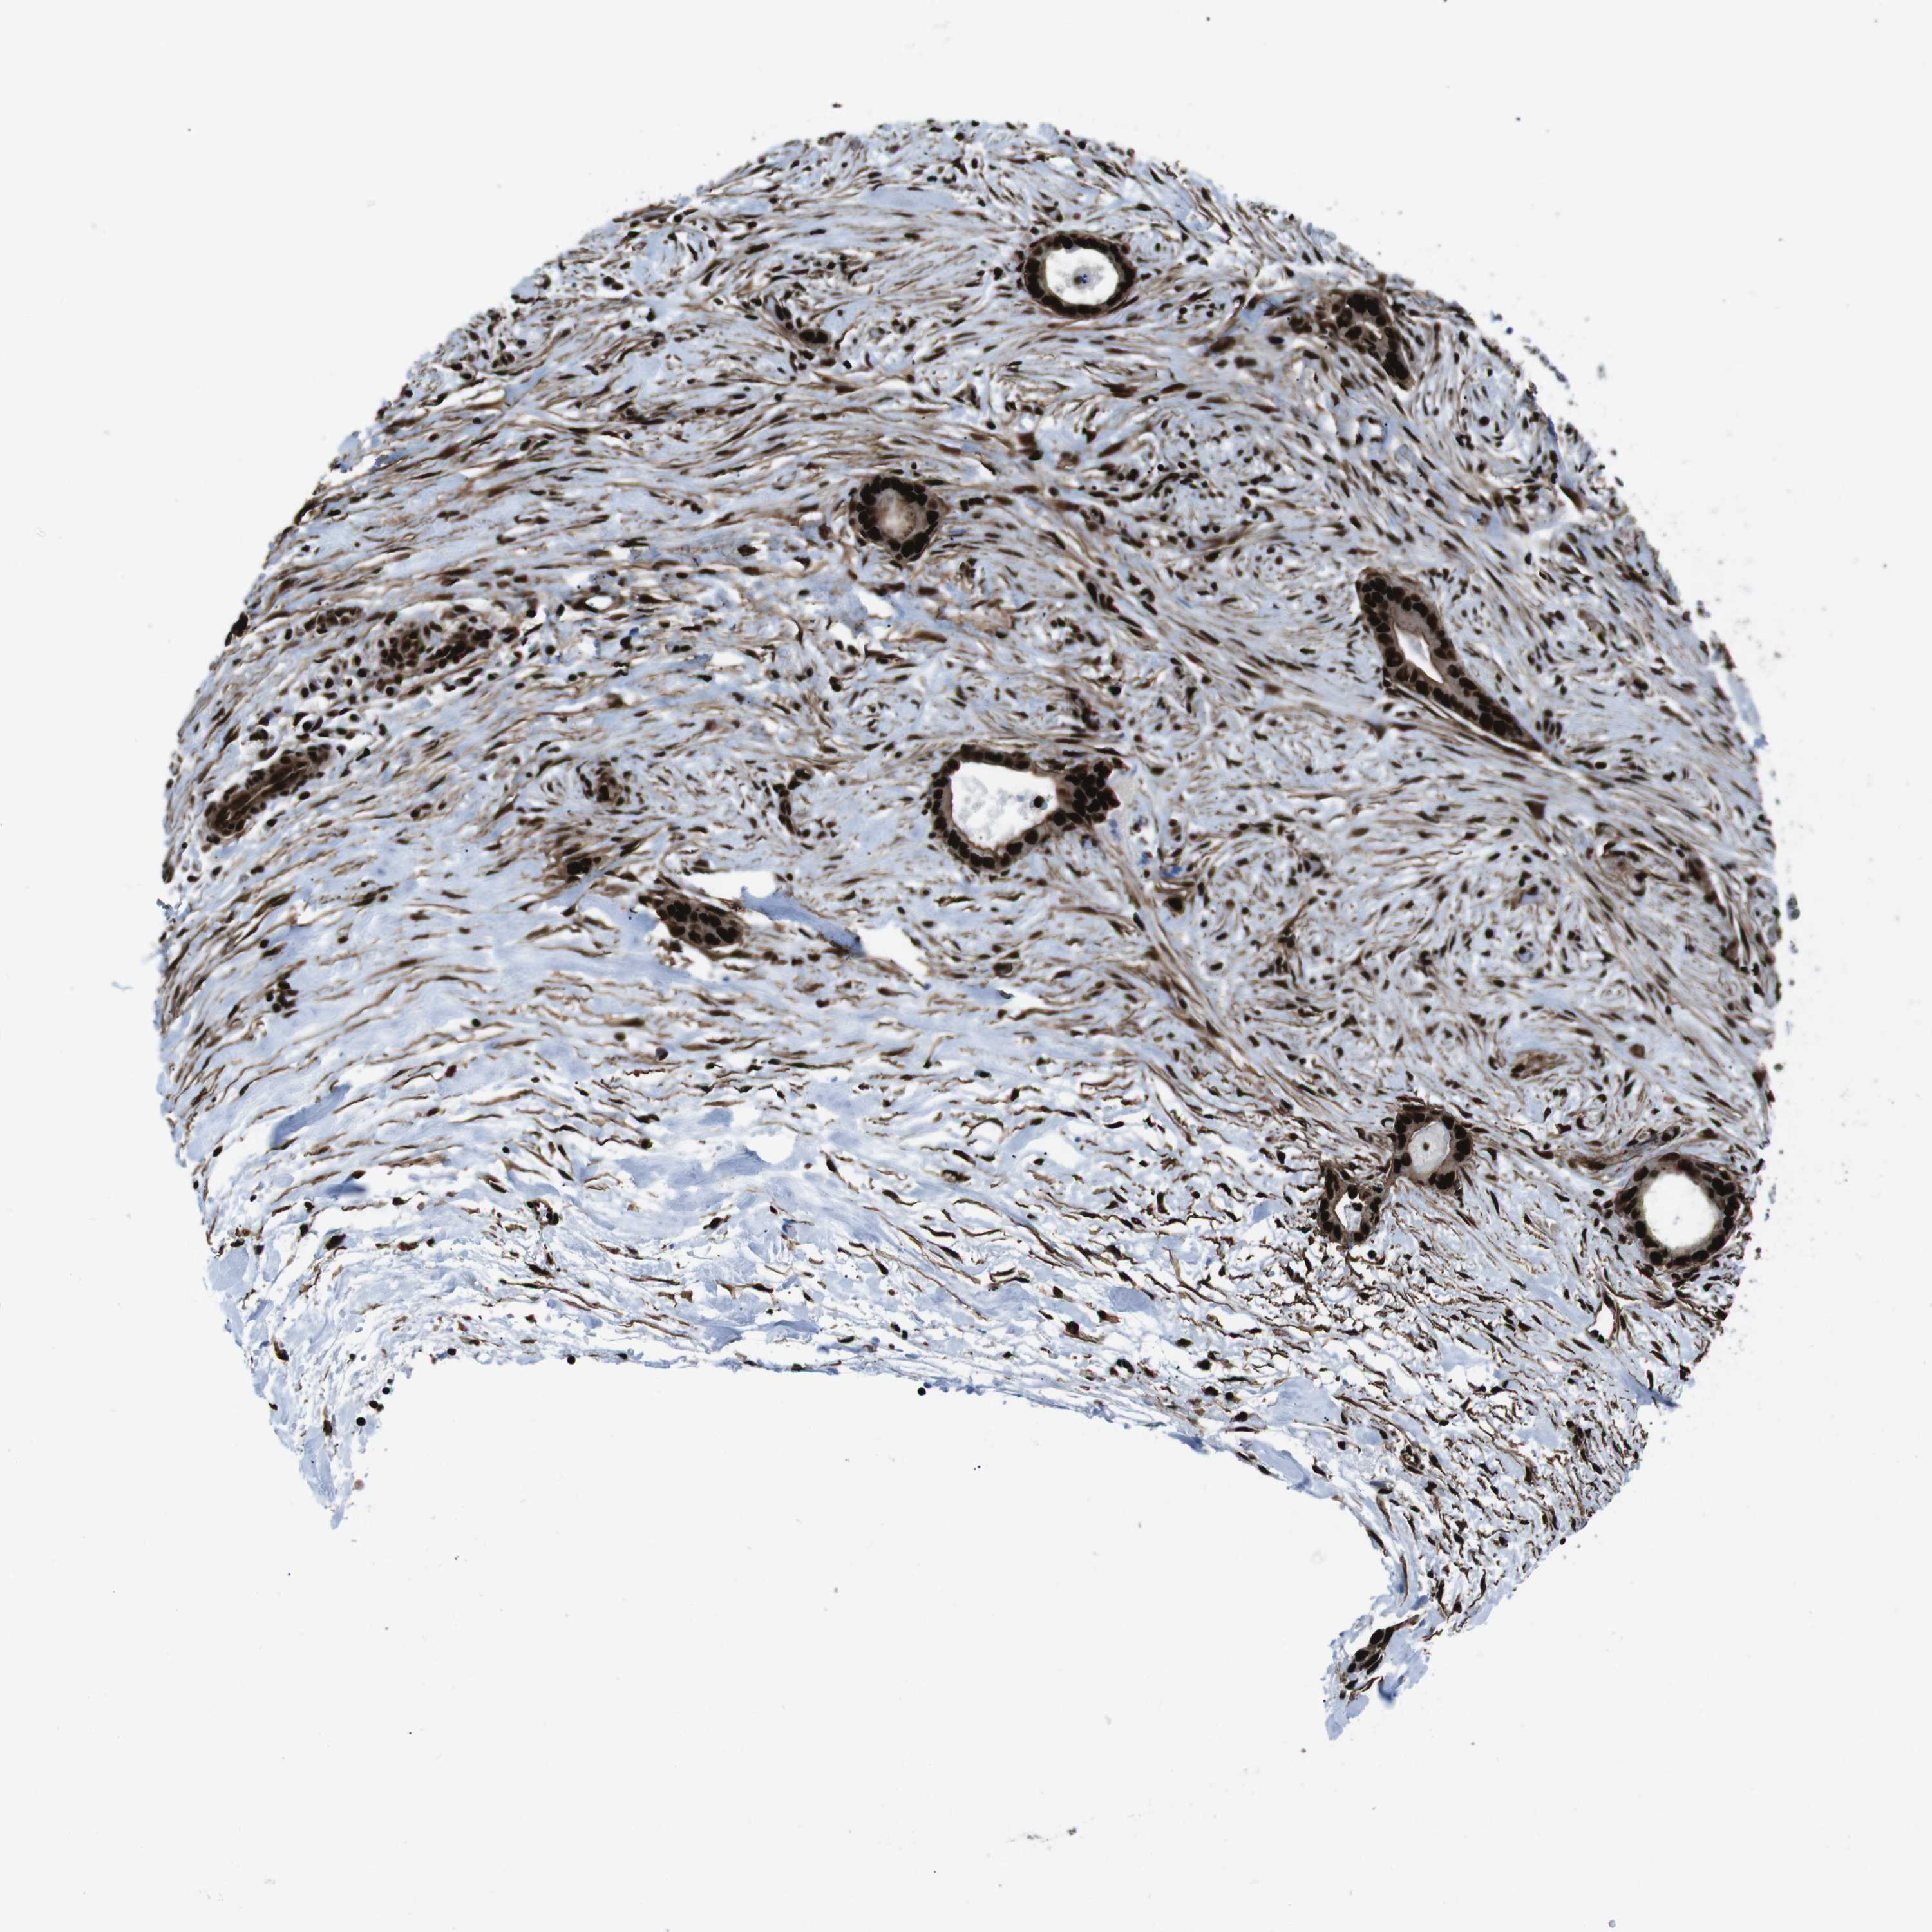

LIVER CANCER - Protein expressioni

A mouse-over function shows sample information and annotation data. Click on an image to view it in a full screen mode. Samples can be filtered based on level of antibody staining by selecting one or several of the following categories: high, medium, low and not detected. The assay and annotation is described here.

Note that samples used for immunohistochemistry by the Human Protein Atlas do not correspond to samples in the TCGA dataset.

Antibody stainingi

Antibody staining in the annotated cell types in the current human tissue is reported as not detected, low, medium, or high, based on conventional immunohistochemistry profiling in selected tissues. This score is based on the combination of the staining intensity and fraction of stained cells.

Each image is clickable and will lead to virtual microscopy that enables deeper exploration of all samples and also displays staining intensity scores, fraction scores and subcellular localization as well as patient and tissue information for each sample.

Antibody HPA041057

Antibody HPA058707

Antibody CAB011532

Staining

High

Medium

Low

Not detected

Intensity

Strong

Moderate

Weak

Negative

Quantity

>75%

75%-25%

<25%

None

Location

Nuclear

Cytoplasmic/membranous

Cytoplasmic/membranous,nuclear

Cholangiocarcinoma

Carcinoma, Hepatocellular, NOS